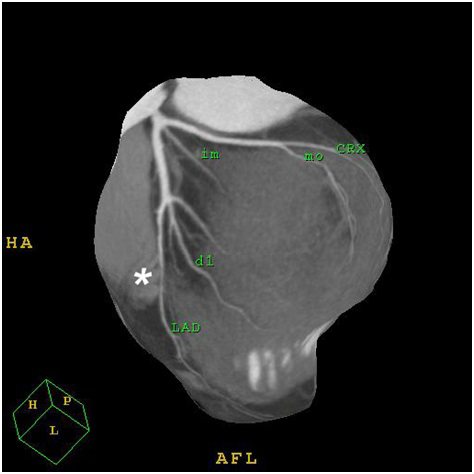

Figure 2: 3 D image of the left coronary artery;

LAD: left descending coronary artery; CRX: circumflex artery; D1: diagonal branch; MO: marginal branch; IM: intermediate coronary artery; star: indicates the tunnelled segment in the mid LAD.